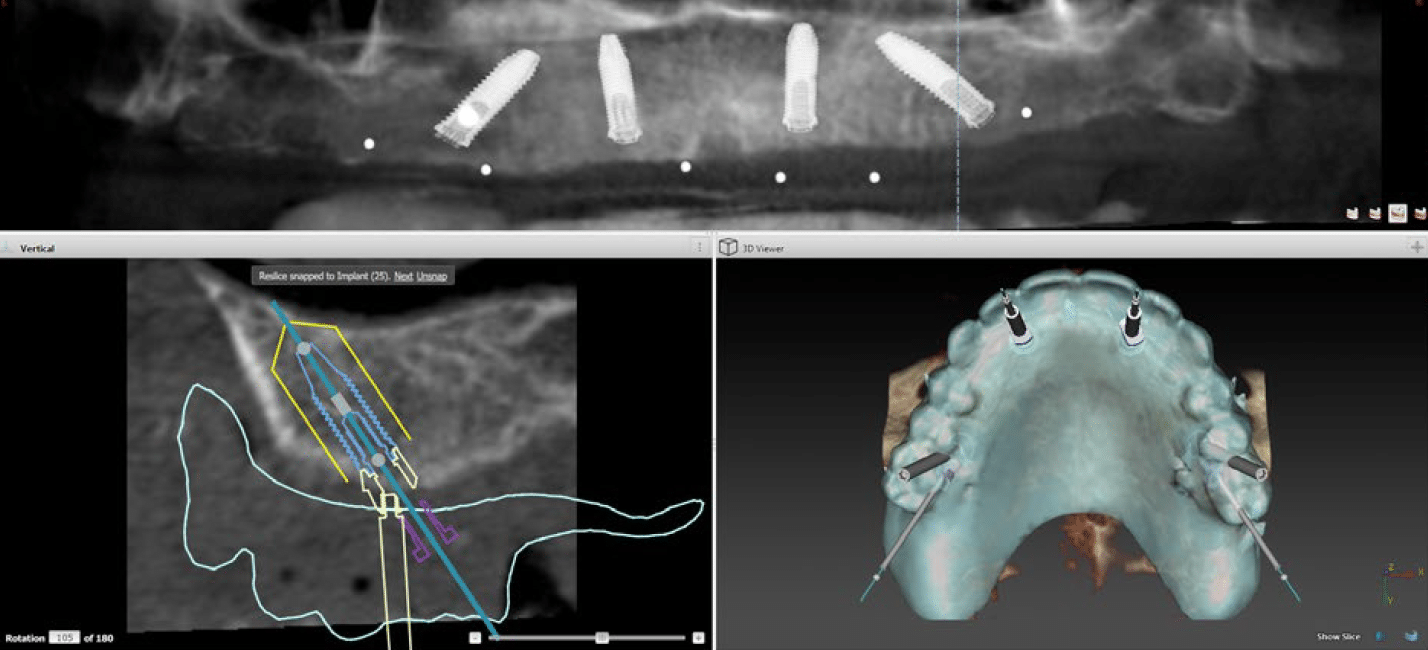

All-on‑4 bezeichnet ein Implantatsystem, bei dem eine komplette Zahnreihe auf lediglich vier strategisch platzierten Implantaten befestigt wird. Zwei Implantate werden gerade im vorderen Kieferbereich eingesetzt, zwei weitere in einem Winkel im hinteren Bereich — so wird maximale Stabilität auch bei geringerem Knochenangebot erreicht.

All-on‑4 eignet sich für Patienten, die mehrere oder alle Zähne verloren haben oder bei denen ein vollständiger Zahnverlust absehbar ist. Auch Patienten, die bisher aufgrund zu geringer Knochenmenge kein Implantat erhalten konnten, kommen häufig für All-on‑4 in Frage. Eine genaue Beurteilung erfolgt nach einer umfassenden Untersuchung mit 3D-Röntgen.